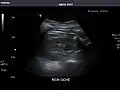

Pancreas